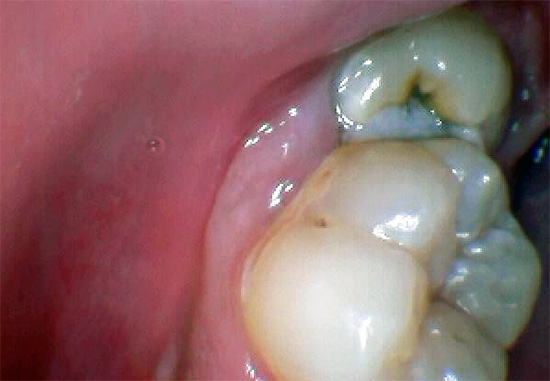

Pertanto, un forte dolore indica spesso un processo infiammatorio sotto il cosiddetto cappuccio gengivale - un tessuto molle sopra il dente che li danneggia.

Oltre al dolore, si notano gonfiore e arrossamento delle gengive. Nel tempo, le forme di pus sotto il cappuccio di un dente del giudizio, la temperatura può aumentare, si verifica spesso mal di testa, l'appetito diminuisce, la salute generale peggiora e appare debolezza. Durante la deglutizione, può verificarsi dolore sul lato in cui cresce il dente del giudizio, a volte la gola, l'orecchio e persino l'intera mascella fanno male.

Quando dentano i denti del giudizio, spesso hanno una banale mancanza di spazio: possono crescere lateralmente e verso il vicino più vicino. In generale, i denti del giudizio inferiori sono i più problematici, poiché quando esplodono compaiono di solito uno o due tubercoli, ricoperti di una gomma, come un "cappuccio", sotto il quale, come in un "bidone della spazzatura", il cibo viene costantemente riempito e marcito.

La pericoronite si forma sullo sfondo dell'attività della microflora batterica, che trova un ambiente favorevole per la vita e la riproduzione sotto il cappuccio gengivale del dente del giudizio. Oltre alla formazione di essudato purulento sotto la gomma, spesso c'è anche una lesione meccanica alla zona gonfia della gomma che si gonfia a causa dell'infiammazione, coprendo il dente del giudizio, a seguito del quale si formano erosioni e ulcere sulla sua superficie, peggiorando le condizioni dei tessuti circostanti e provocando forti dolori alla gomma e alla guancia.